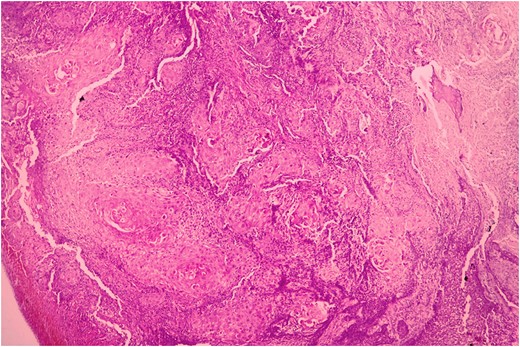

Biopsy was taken from hypertrophied and ulcerated lesion. On microscopy, tissue was lined by keratinized stratified squamous epithelium with surface ulceration. Underlying stroma showed infiltrating squamous cell carcinoma (SCC) along with extensive collagenous fibrosis (Fig. 2). Dense acute and chronic inflammations were also noted. A diagnosis of SCC with familial gingival fibromatosis was given (Fig. 3).

Histopathological picture showing islands of squamous cell carcinoma infiltrating into the stroma. (H&E, ×400).